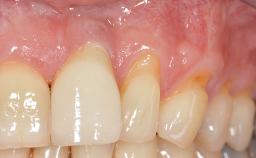

A 30-year-old woman was referred by her general dentist for evaluation of an esthetic complication related to previous implant treatment for congenitally missing maxillary lateral incisors. The patient’s chief complaint was the inadequate esthetic appearance of her smile. The case demonstrates the use of a combined approach to achieve optimal results. Two different flap designs - a tunnel technique and a coronally advanced flap - are employed based on the surgical objectives for the affected site.

Soft Tissue Grafting Yes

Soft Tissue Anatomy Intact Defective